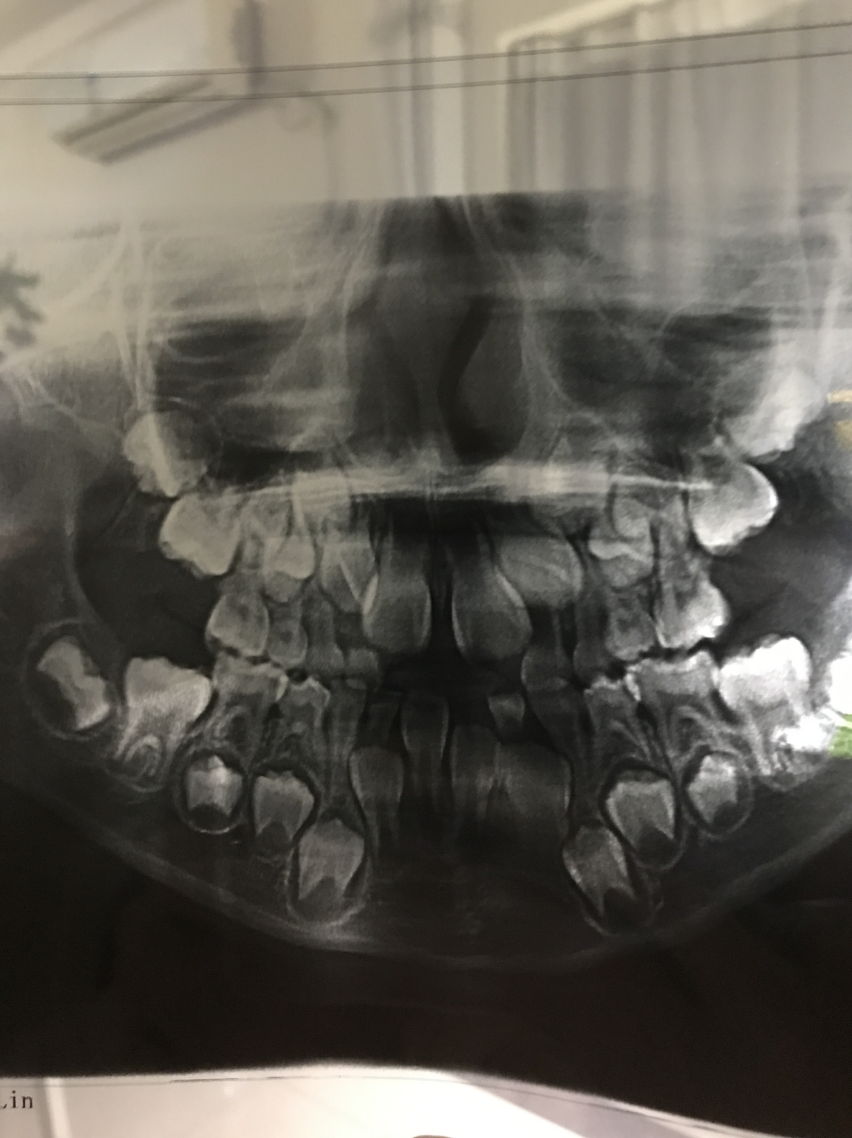

儿童牙齿X线可看到有两副牙齿, 即乳牙和恒牙。

儿童时期的牙齿主要是乳牙和年轻恒牙。每个牙齿的发育时间虽然不尽相同,但是都是经过生长期、钙化期和萌出期3个阶段,通过X光可以看到乳牙根分叉度大,牙根有生理性吸收,在其下方还有一副正在发育的继承恒牙,后方还有未萌出的第一、二恒磨牙牙胚。

虽然x光片看起来吓人,但是藏在口腔骨骼内的“另一排牙齿”实际上只是牙胚,尚未完全钙化 ,也并没有生长到牙齿完全体状态。

这都是正常的生理现象,是一个不断生长发育的动态变化过程,不会有不舒服的感觉!乳牙从6个月开始萌出,2岁半到3岁长到20颗牙齿。然后从6周岁开始脱落,替换出恒牙,这个过程持续到12周岁左右。所以,小朋友还是要爱护我们的牙齿,好好刷牙,剔牙,减少零食次数,戒断夜食夜奶,零食集中吃,吃完刷牙剔牙!定期去看牙医也必不可少!